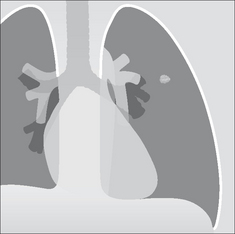

image

Figure 20.3 SPN at the apex of the left lung. The margin is slightly irregular and ill-defined. These two features are suggestive of a primary bronchial carcinoma.